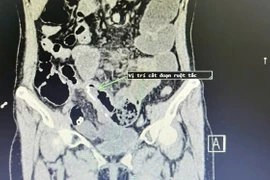

Ngày 15/5, Bệnh viện Đa khoa tỉnh Tuyên Quang cho biết vừa phẫu thuật thành công cứu sống người bệnh 49 tuổi, bị tắc ruột do dây chằng sau mổ.